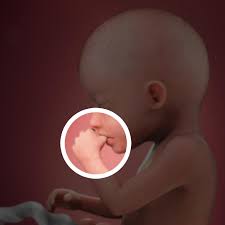

I was exactly 20 weeks yesterday. At about 165 centimetres 65 inches long by 20 weeks pregnant your babys weight is about 283 grams 10 ounces which means that she would be a wee bit lighter than a can of soda in your hand. My little girl was also 11 oz at 20 weeks and the doctor said it was perfectly average a.

Your baby is almost a pound. This week heshe is about 63 in 16 cm from the top of the head to the coccyx and about 98 in 25 cm from head to toe. Your baby is as big as a sweet potato.

Youre 20 weeks along which means youre already halfway through your pregnancy. My daughter was 11 at 19 weeks and for the rest of my pregnancy I measured a week ahead she was born after her due date by induction and weight 8 lb 11 oz so she was big but not abnormally large or anything. The 20-week baby weighs 106 oz 03 kg.

At about 165 centimetres 65 inches long by 20 weeks pregnant your babys weight is about 283 grams 10 ounces which means that she would be a wee bit lighter than a can of soda in your hand. 20th percentile My doctor thinks this is small for 20 weeks and wants me back for a growth check US at 24.